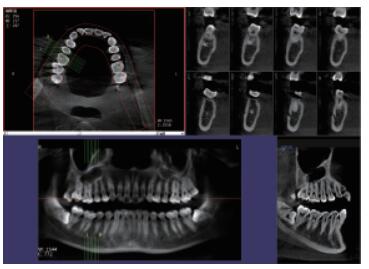

在口腔影像等細分領域,口腔CBCT的成像質量優(yōu)于CT和普放。CBCT的X線利用率更高,且生成的圖像具備很高的各項同性空間分辨率。口腔CBCT能夠針對局部斷層曲面重建生成清晰無重疊的斷層影像以及3D影像,成像效果更好,有助于醫(yī)生的診斷,對于種植、綜合診斷、正畸等牙科診斷均有較大幫助。口腔CBCT技術優(yōu)勢如下:

三維重建任意斷層

專有三維重建算法,可提供任意位置高清斷層影像。

高清口腔全景影像

通過三維容積影像,提取高清口腔全景影像。

多平面組合重建

可同時觀察軸向面、冠狀面和矢狀面圖像,方便臨床診斷。